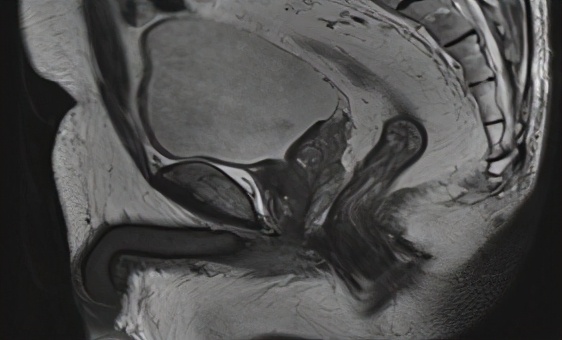

男性,78岁,肿瘤距肛2.5cm,T2N0,拒绝永久性造口手术。知情同意后建议新辅助放化疗后争取观察等待疗法。接受50Gy放疗+卡培他滨同期化疗增敏。放疗结束6周后肿瘤临床完全缓解,患者接受观察等待疗法,观察至今5年无复发,肛门功能完全正常,生存质量良好。

图2b 治疗前MRI(2015.6)